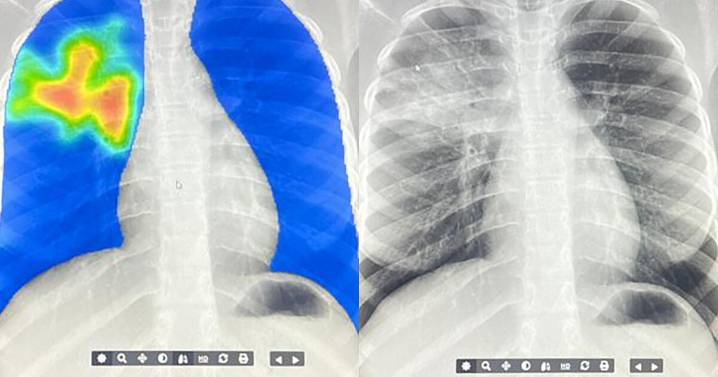

The difference? A mobile x-ray machine and an AI algorithm are detecting TB. (In case you're not familiar with AI terminology — this is basically a computer program trained on a whole lot of data.)